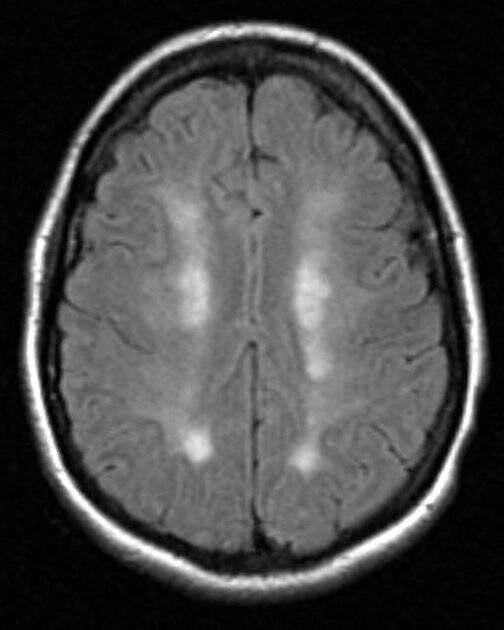

On the scans a 'rosary' pattern can often be recognized; an elongated pattern. See the images below:

Case courtesy of A.Prof Frank Gaillard, Radiopaedia.org. From the case rID: 2626 and the case rID: 5199